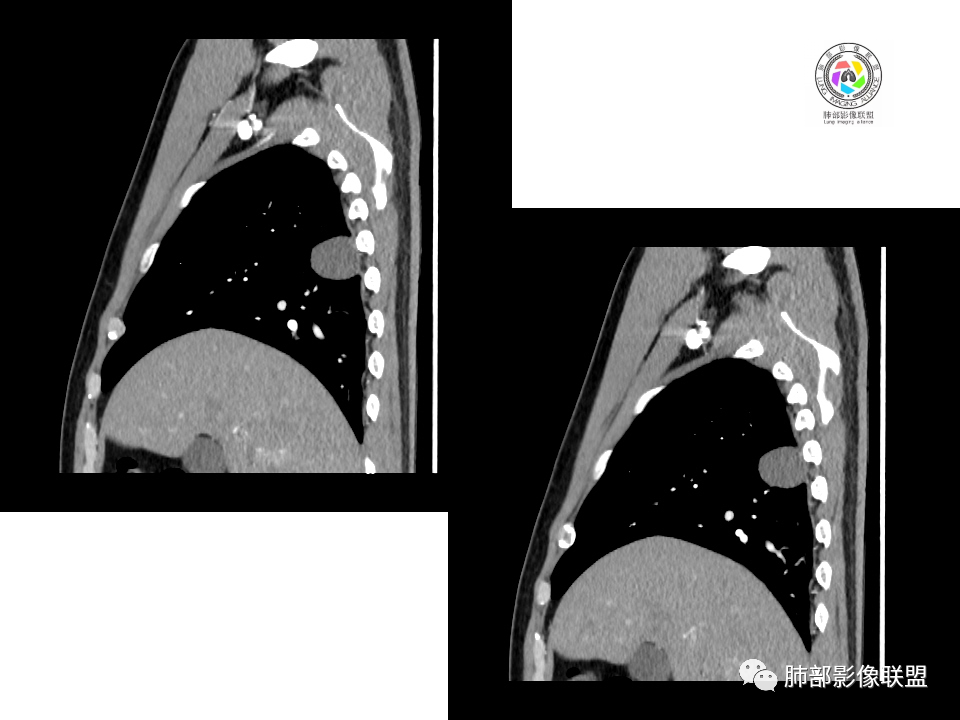

中年男性,体检发现占位。右肺下叶背段胸膜下肿块,周围晕征,有小分叶,与支气管、肺内血管关系不清,形似山丘,重建可见肿块呈D字形凸向肺部。似跨斜裂,似有小凸起与肋下缘相连,增强似有轻微均匀强化。右肺下叶外基底段小结节,位于血管周围,部分边缘平直,轻微均匀强化。考虑二元:一、右下叶背段肿块为肺外病变,神经鞘瘤?SFT?鉴别小细胞癌、隐球菌病;二、右下叶外基底段结节考虑为良性结节、炎性肉芽肿?

右肺下叶占位,胸膜下,与胸膜关系密切;

密度均匀;糊墙,边缘膨隆为主;

部分血管推移。

2.右肺下叶背段胸膜下块影,边界清楚光整,上下极见磨玻璃晕,未见明显分叶毛刺和棘状突起,未见胸膜凹陷或胸壁侵入。密度均匀,轻度不均匀强化。未见支气管进入。

显然本例焦点在于背段那个边缘光整的块影!

4.良性占位绕不过去,如发生于该部位的孤立性纤维瘤等……

病灶不均匀强化可以将含液支气管囊肿排除在外。

有老师分析,多发病灶有磨玻璃晕,可以符合隐球菌感染,确实如此。但背段边缘如此锐利的块影还是更容易让人联想到新生物。